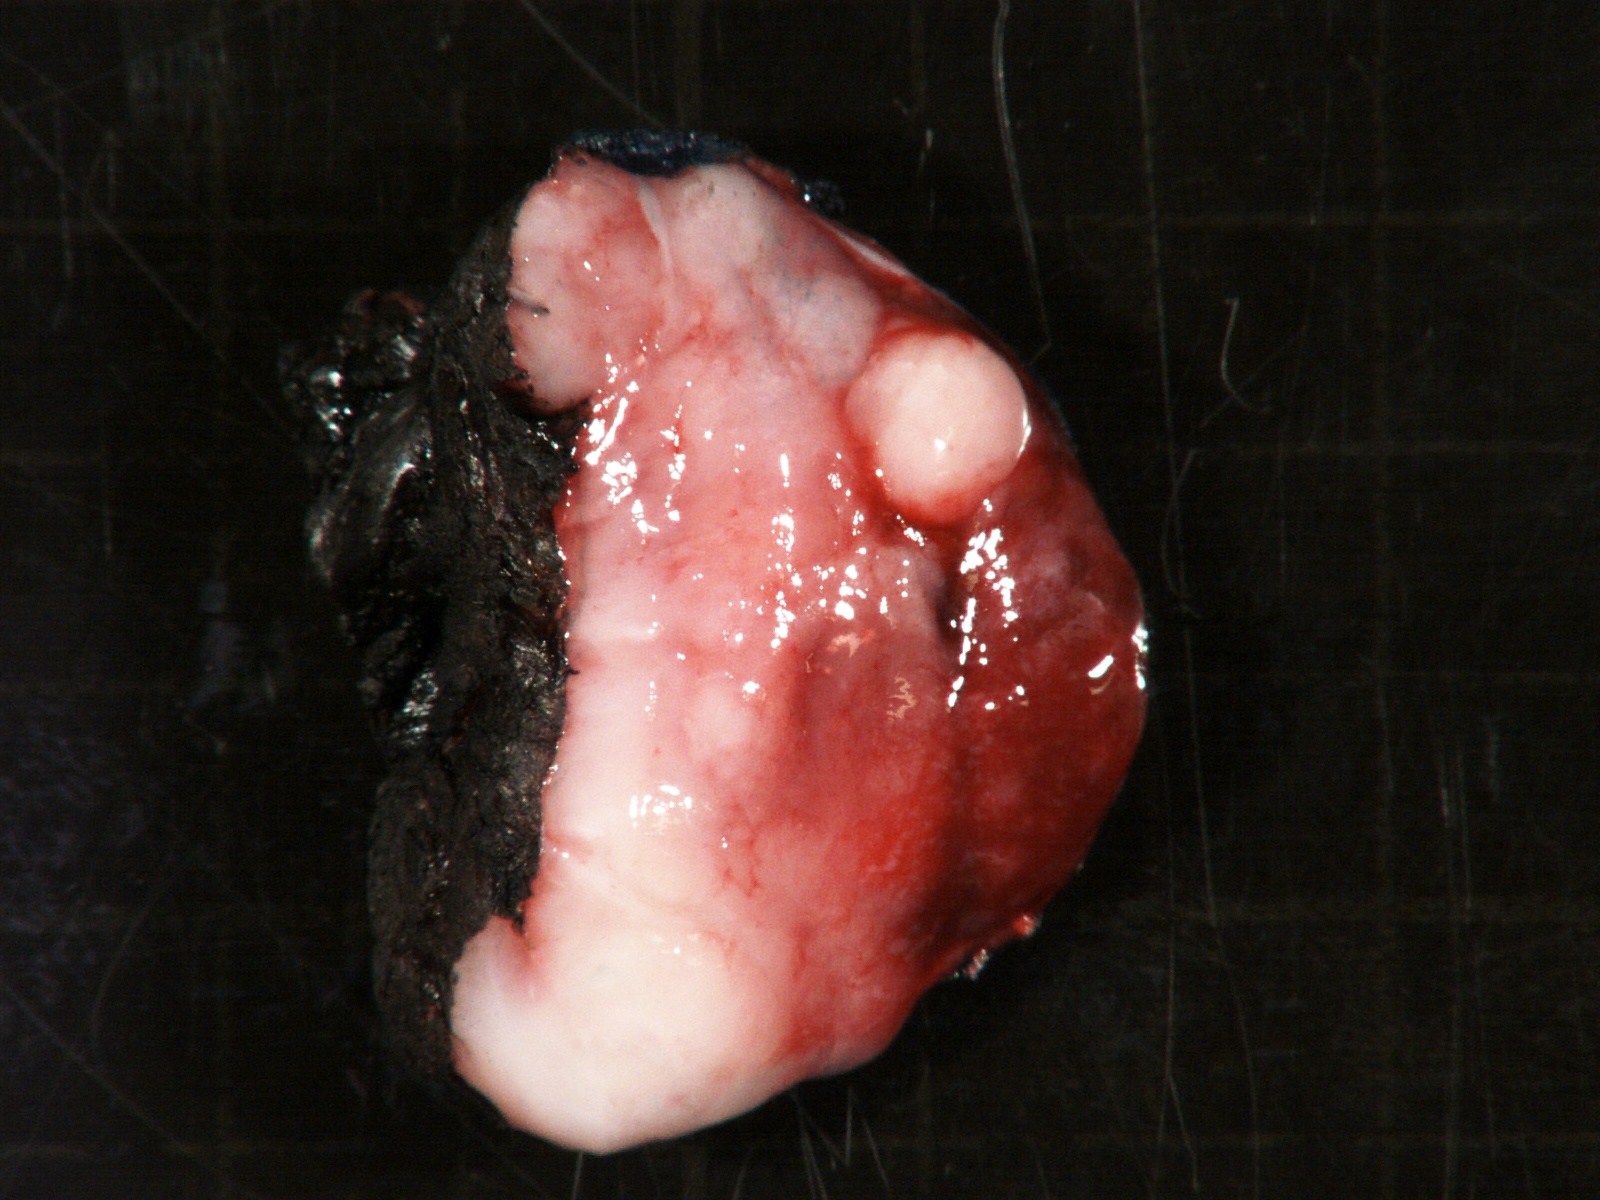

- More homogeneous and mature appearance than neuroblastoma

- Varies by subtype, from circumscribed ovoid mass to large multilobulated tumor

- Stroma rich, nodular subtype: area(s) of stroma poor, immature tumor are usually hemorrhagic with well defined borders (J Natl Cancer Inst 1984;73:405)

- Calcification (chalky white, yellow areas) and cystic degeneration may occur

- If large, adrenal gland may be difficult to identify